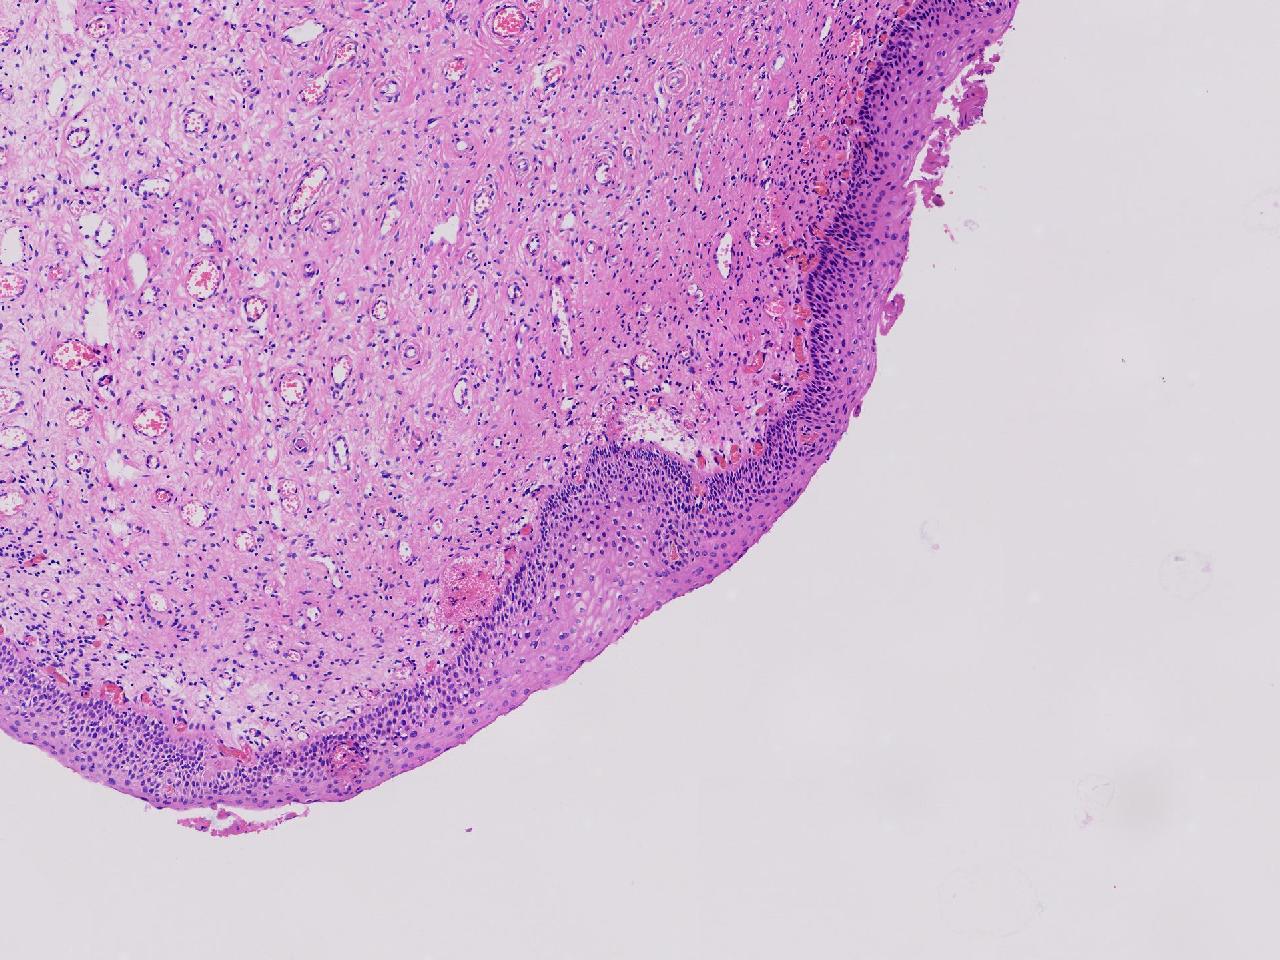

CIN1级? CIN2级?

性别年龄61岁临床诊断

一般病史女,61岁,宫颈活检,,HPV6+ 52+

标本名称宫颈活检

大体所见灰白色不整形软组织1块,直径0.3厘米。

CIN2倒是不够,图3有几个像挖空细胞,HPV有阳,勉强可以考虑小灶LSIL。

• zhuang xia nan:  是的。  2级肯定不够,有挖空细胞,小灶1级。    谢谢老师指点。

CIN1.